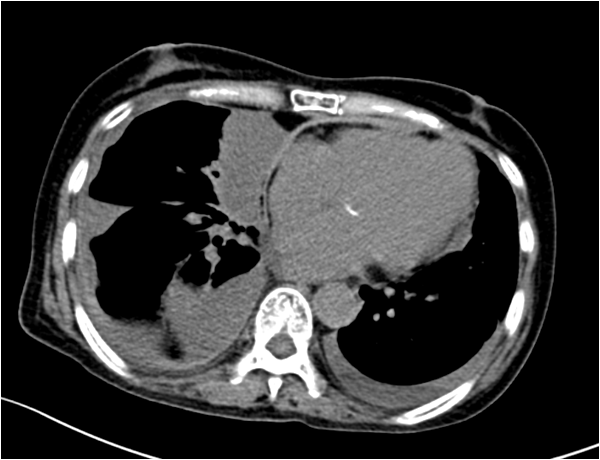

心脏CT

心包影宽,密度增高,考虑心包不规则增厚,双侧胸腔及叶间积液